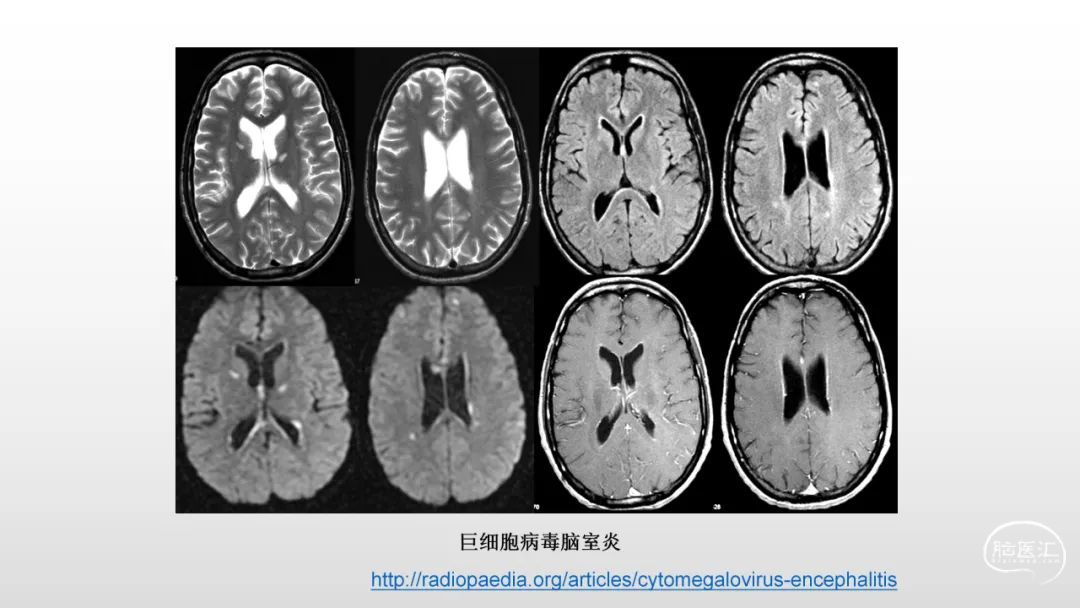

颅脑影像诊断基础知识讲座:感染和免疫性疾病2